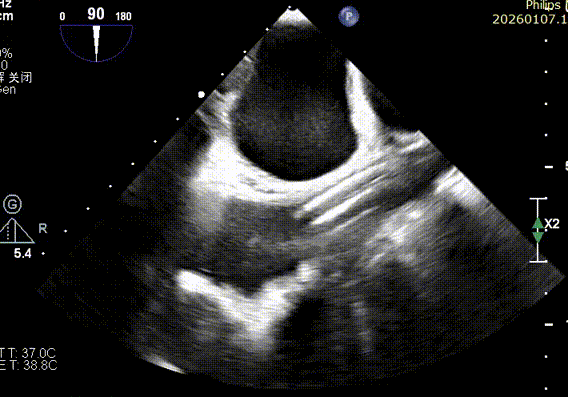

Preoperative precise assessment by transthoracic and transesophageal echocardiography (TTE/TEE) revealed:

Mitral valve: severe functional regurgitation (4+), effective regurgitant orifice area (EROA) 0.52 cm², regurgitant volume 68 mL.

Tricuspid valve: Type IIIb quadricuspid malformation with insufficiency, secondary severe regurgitation (4+), mild annular dilatation (mean diameter 40 mm), mean vena contracta 10 mm. Regurgitant orifices are located at anteroseptal, central, and posteroseptal regions, with marked enlargement of the right atrium and right ventricle.

Preoperative Imaging

Mitral regurgitation

3D color Doppler

Mitral valve Zone 2

Color Doppler of Mitral valve Zone 2